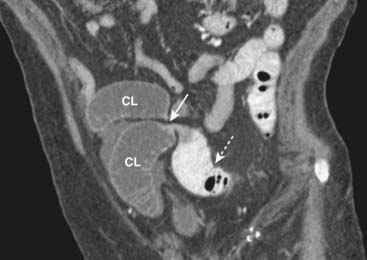

Figure 14-14 Large bowel obstruction masquerading as a small bowel obstruction.

There are air-filled and dilated loops of small bowel (solid white arrows) seen in this patient who had a mechanical large bowel obstruction from a carcinoma of the middescending colon. The pressure in the colon was sufficient to open the ileocecal valve, which then allowed much of the gas in the colon to decompress backward into the small bowel. The cecum still contains air (dotted white arrow) and is dilated, a clue that this is really a large bowel obstruction. Abdominal CT can resolve the question of whether the large or small bowel is obstructed.